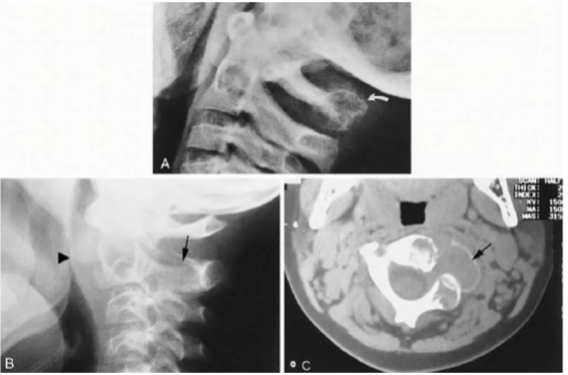

Hémangiome : Bénin mais DOULOUREUX

- 1er plus commune tumeur bénigne de la colonne (squelette axial)

- F > H , > 40 ans

- La majorité des lésions sont dans la colonne

- Colonne : « CORDUROY CLOTH »

- Crâne : « SPOKED-WHEEL APPEARANCE »

- Si apparence de plusieurs hémangiomes, c’est de l’ostéoporose

- DDX : Maladie de paget (mais dans ça, les contours vertébraux sont sclérotique (picture frame vertebrae).